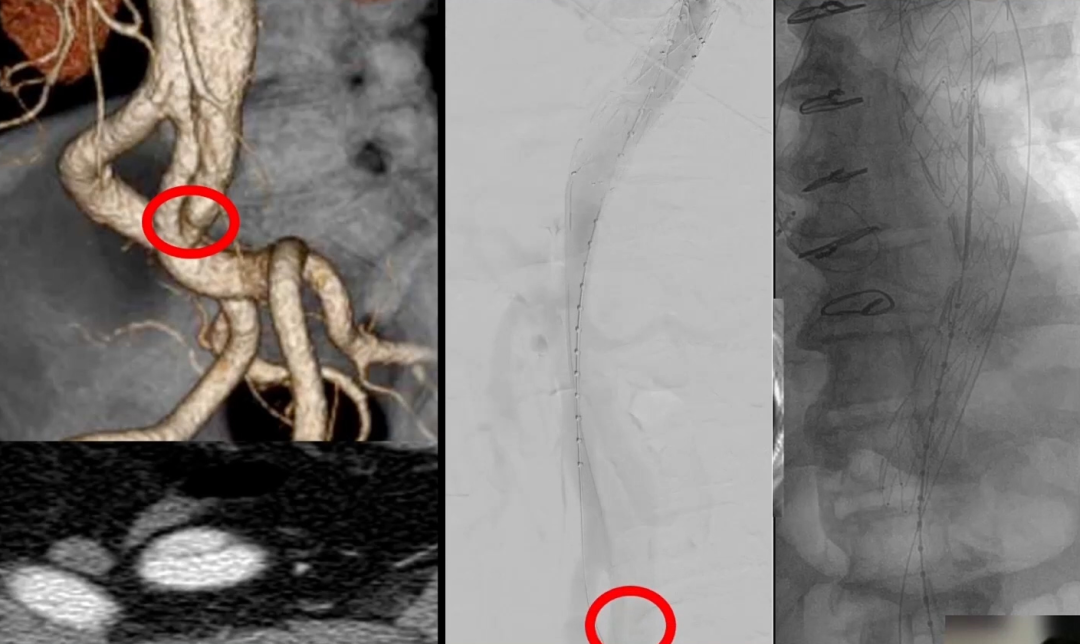

可以通过夹层裂口或者破膜进入假腔放置栓塞材料,并借助术前CTA、影像融合以及IVUS的辅助。

举一个在髂总动脉继发破口处进入假腔的一个例子:

使用IVUS定位导管进入假腔的位置,进行弹簧圈或者血管塞的栓塞,可以将其比作往“假腔里扔垃圾”。

术后CTA也显示“假腔内垃圾”的效果良好,成功堵塞了假腔。同时我们需要注意的是,在这个阶段正确的影像学辅助的重要性。

另一个例子是,在假腔内送入弹簧圈、血管塞甚至打胶栓塞,以便诱发阻塞或血栓形成,如下图所示。

但是,对使用此技术的患者必须要进行严格随访,特别是必须检查静脉期CT成像,寻找和确认假腔内是否仍存在持续血流。